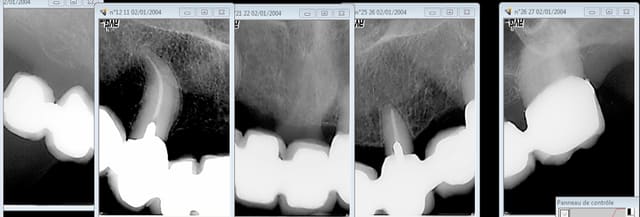

Ma grand mère est ma seule patiente qui a atterri aux urgences à cause d'une hémorragie suite à une extraction. Et voilà le genre de conneries qu'on fait pour lui remplacer son Stellite qu'elle ne supportait plus à 89 ans car très fortement diminuée. En croisant les doigts pour que ca ne se casse pas la gueule.

Il a tenu jusqu'à sa mort à 92 ans. All on 4. -)

C'est tout aussi acrobatique sur ma mère qui ne veut pas entendre parler d'implants.

Tout ceci tient par miracle depuis 15 ans. mais ca peut encore aller pour 74 balais. -)